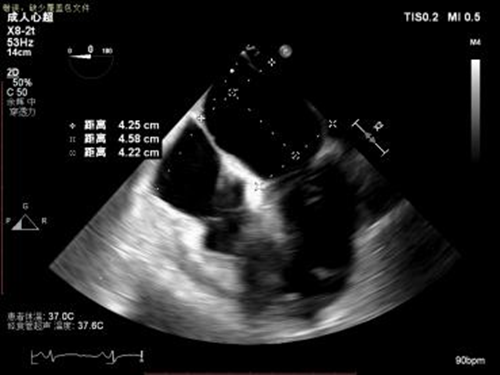

1.四腔心切面和二腔心切面可见左室高侧壁室壁瘤形成,二尖瓣瓣叶脱垂伴重度反流。

3D MV View: 二尖瓣前后瓣叶对合不全,A2/P2稍偏1区可见未闭间隙。PISIA主要来源于A2/P2区域。